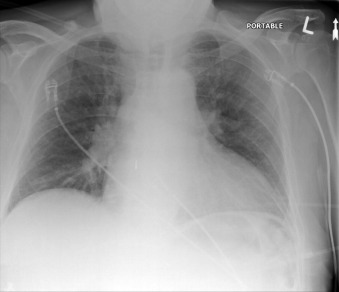

The Impella 5.0 (5.0 L/minute support) is inserted by surgical cutdown or via sternotomy ( Graphic 24-1; Figs. 24-8 to 24-13 ). There are two models. The Impella 5.0 is similar to that described previously. The Impella 5.0 LD is similar but without the pigtail component.